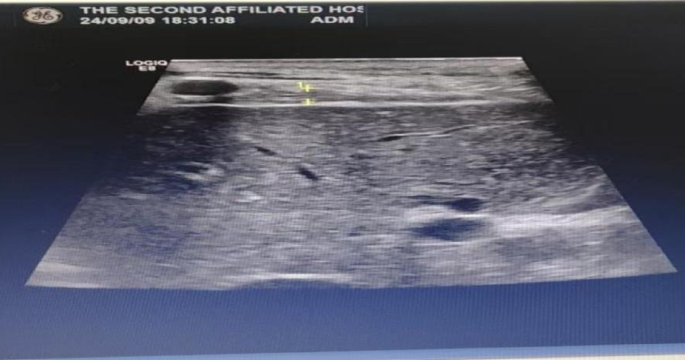

② Diaphragm thickness and diaphragm thickening fraction

The patient is in a supine position, and a linear array probe with a frequency of 7–13 Hz is placed between the 7th or 8th rib of the right anterior axillary line, which is the area where the diaphragm meets the chest wall. The movement of the diaphragm is scanned, and the distance between the parallel high echo inner sides of the diaphragm on both sides is measured, which is the diaphragm thickness. Measure the end-inspiratory diaphragm thickness (DTei) and end-expiratory diaphragm thickness (DTee) under calm breathing for three respiratory cycles, and calculate the average value. Obtain the diaphragm thickening fraction DTF = (DTei DTee)/DTee × 100% through the formula. See Fig. 4.

Schematic diagram of diaphragm thickness measurement (right side).